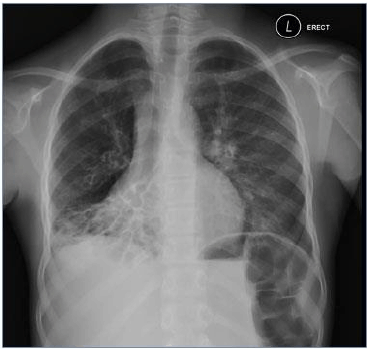

Considere a imagem radiológica abaixo:

http://www.residenciapediatrica.com.br/detalhes/285/leituras-de-radiografias-de-torax-em-criancas-suspeitas-de-possuir-tuberculose-pulmonar

A imagem acima, demonstra, perda de volume do lobo médio e inferior direito, com anéis de sinete típicos visíveis na região pulmonar afetada, altamente, sugestivo de: